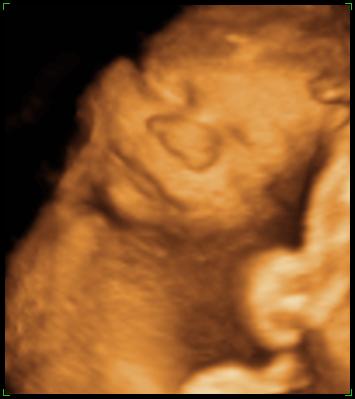

27 Week 3D/4D Scan on 04 May 2006